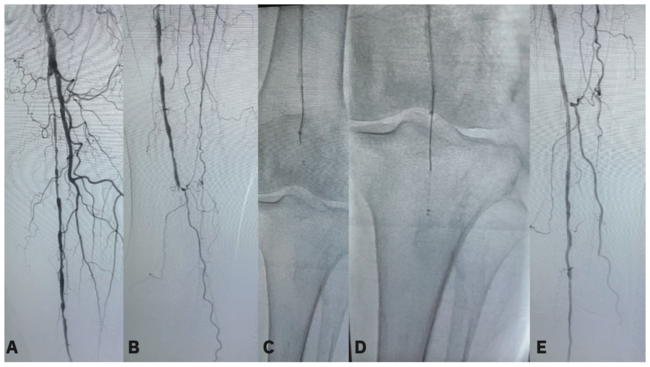

Patients with CLI tend to have more advanced disease, and I would say that in 70%-80% of our patients, we need to cross a CTO to effectively revascularize their leg. It is important to do everything we can to maximize flow all the way down to the level of the tissue in the foot, and sometimes it does involve interventions below the ankle, within the pedal arch vessels, to maximize flow, which could help to improve limb preservation. CTOs represent some of the most difficult anatomy in peripheral artery disease. We now also have retrograde options, including pedal access or retrograde superficial femoral artery (SFA) access. The reason that we have developed all these different techniques like antegrade wire escalations, is because tools can still be unsuccessful when crossing challenging CTOs. Simply put, if you can’t get a wire across, you are not able to deliver subsequent devices and the case will be unsuccessful. That’s why devices like the Crosser iQ™ CTO Recanalization System (Becton, Dickinson and Company – Figure 1) are so important, to help increase the chances of crossing peripheral artery CTOs.

CTO cases can be divided into two categories. The first involves difficulties in remaining true lumen. Other devices may get subintimal and get near the distal cap, but then it takes other additional devices, time, and cost to reach the true lumen of the ongoing vessel. By centering the wire and with its unique mechanism of action that automatically and selectively ablates the plaque while remaining atraumatic to elastic tissue, the Crosser iQ™ CTO Recanalization System can help facilitate staying true lumen. The importance of that can’t be understated, because once you get subintimal, it often adds another 20 or 30 minutes to the procedure time to get back into the true lumen. It also removes some of the other treatment options. Once you are subintimal, it becomes more difficult or can change the risk-benefit ratio for the use of atherectomy devices or other vessel preparation tools that may help increase the long-term patency of the artery. The second category of cases involves CTOs with a very hard cap that may be difficult to penetrate, even with a standard wire. In each of these categories, the Crosser iQ™ CTO Recanalization System has an important role. First and foremost, it has a unique mechanism of action specifically designed to help you cross peripheral CTOs intraluminally. The Crosser iQ™ CTO Recanalization System uses a wire-based approach with the Recon™ Crossing Support Catheter and the device itself, which means it fits very easily into the standard workflow of the cath lab. The fact that you can integrate the crossing system with a support catheter is a major benefit. The device delivers ultrasonic energy by automatically adjusting its power output to help stabilize the distal tip of the catheter to assist in penetrating the CTO cap. The Crosser iQ™ Ultrasonic CTO Device’s ability to cross a lesion from the antegrade approach has also helped to both speed up the case and increase the overall likelihood of my crossing success. In my experience, I have seen multiple cases where the cap of the CTO has been very hard and difficult to penetrate, even with a very high gram tip wire. I used the Crosser iQ™ Ultrasonic CTO Device and it had very good penetration capacity on harder caps. Once we got through the cap, I have been very impressed with how the device tracked through the chronically included mid segments of the occluded artery to ultimately reach the distal cap, often accomplished in just two or three minutes, which is quite efficient. For operators who are developing their practice, the Crosser iQ™ CTO Recanalization System is a device that can help increase their overall efficiency and is an important addition to our armamentarium for the effective treatment of patients with CLI who have peripheral artery CTOs.

The goal should be to advance the catheter just two to five millimeters per second, which allows time for the Crosser iQ™ Ultrasonic CTO Device to do its work at the front end of the cap and avoid displacing away from the chronically occluded segment into a sub plane. Another important technical tip is to maintain the support catheter in the range of 20 to 30 millimeters behind the Crosser iQ™ Ultrasonic CTO Device tip. Having the support catheter near the tip helps provide some additional force and can also provide directionality if you need to redirect the tip of the catheter while advancing. In all the cases I have done with the Crosser iQ™ CTO Recanalization System, I have been able to get through the CTO in under five minutes or I have been able to reach the distal cap in under five minutes. There have been some cases, even in the long segment CTOs over 300 mm, where we could get from the tip of the occlusion to the distal cap in under two minutes. Fluoroscopy offers only a two-dimensional view, so it can be hard to navigate in three dimensions, and in my experience, the Crosser iQ™ Ultrasonic CTO Device can be very helpful to make sure you are orienting in the right plane when crossing an occlusion.

I use it as a frequent upfront device when approaching femoropopliteal CTOs. When I see a lesion that looks like it has a hard cap and a long segment occlusion, then I think the Crosser iQ™ Ultrasonic CTO Device is a great first tool to cross the occlusion, instead of committing upfront to using multiple wires and potentially, a reentry device. The Crosser iQ™ CTO Recanalization System has become an important part of my algorithm when considering an efficient way to cross a femoropopliteal occlusion.